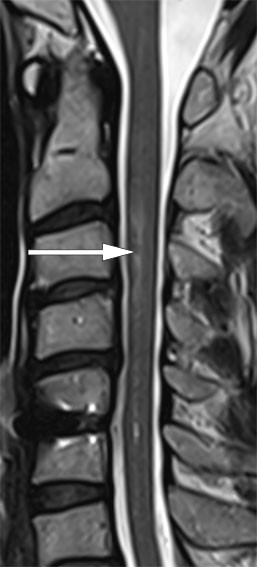

MR-undersøkelsen av hjernen viste funn forenlig med et lite, ferskt infarkt i venstre cerebellarhemisfære. Intramedullært var det nå tilkommet et mer distinkt, økt T2-signal i nivå C2–C4 (figur 1), der aksialt diffusjonsopptak viste restriktiv diffusjon innad i områder med økt T2-signal, som hadde overvekt mot venstre side (figur 2).

Ved klinisk mistanke om akutt medullært infarkt bør det utføres diffusjonsvektet MR-undersøkelse, da T2-signalavvik kan være subtile eller fraværende tidlig i akuttfasen. I nivå C3–C5 kan fremstillingen av medulla være påvirket av ulike bildeartefakter på MR-undersøkelse, noe som kan gjøre deteksjon av signalavvik utfordrende.